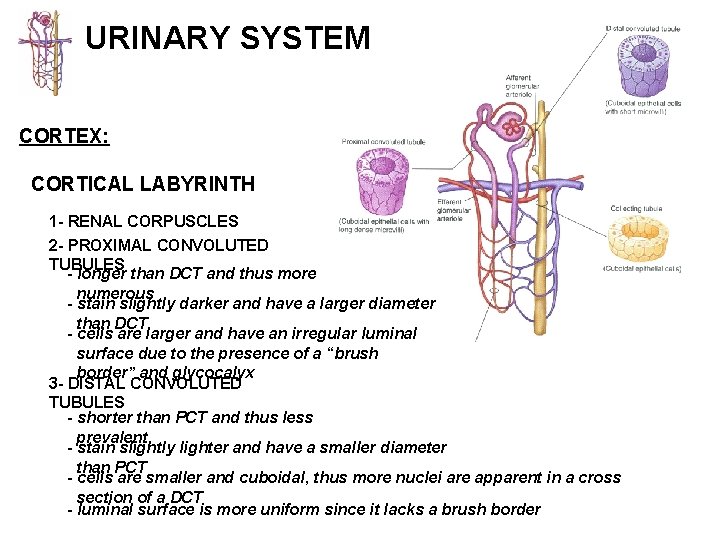

URINARY SYSTEM THE NEPHRON & COLLECTING DUCTS CORTEX: CORTICAL LABYRINTH 1 - RENAL CORPUSCLES 2 - PROXIMAL CONVOLUTED TUBULES 3 - DISTAL CONVOLUTED TUBULES MEDULLARY RAY 1 - STRAIGHT PORTIONS OF PROXIMAL TUBULE (THICK DESCENDING) 2 - STRAIGHT PORTIONS OF DISTAL TUBULE (THICK ASCENDING) 3 - COLLECTING DUCTS

URINARY SYSTEM CORTEX: CORTICAL LABYRINTH 1 - RENAL CORPUSCLES 2 - PROXIMAL CONVOLUTED TUBULES - longer than DCT and thus more numerous - stain slightly darker and have a larger diameter than DCT - cells are larger and have an irregular luminal surface due to the presence of a “brush border” and glycocalyx 3 - DISTAL CONVOLUTED TUBULES - shorter than PCT and thus less prevalent - stain slightly lighter and have a smaller diameter than PCT - cells are smaller and cuboidal, thus more nuclei are apparent in a cross section of a DCT - luminal surface is more uniform since it lacks a brush border